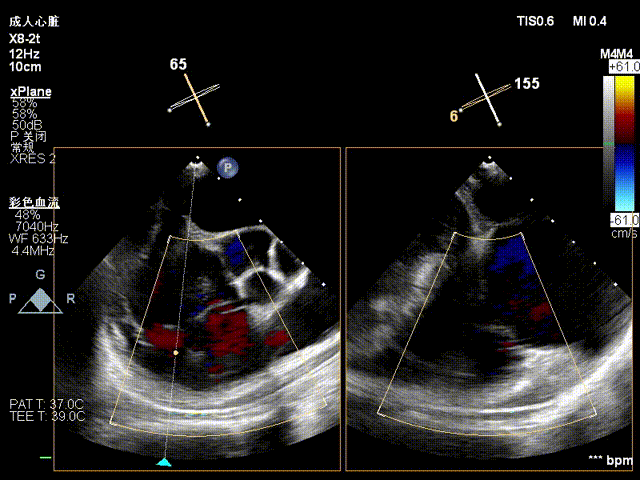

术前超声

术后超声